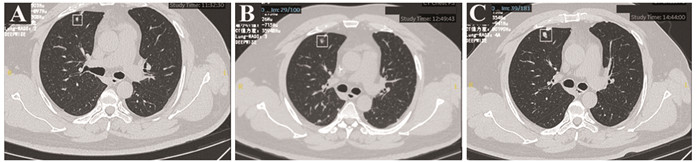

高级别肉瘤患者肺部不确定性质结节胸部CT影像学特征与转归:一项单中心回顾性研究

目的 分析肺部高级别软组织肉瘤患者肺部不确定性质结节(IPN)的影像学特征与转归。

方法 回顾性分析82例伴IPN的高级别肉瘤患者的临床资料,IPN的CT影像学特征以及转归。

结果 IPN平均大小6.453±0.864 mm。IPN直径、形状、密度及结节发现间期可能是恶性转归相关的CT影像特征。年龄(HR=1.047, 95%CI: 1.007~1.088)与结节发现间期(HR=3.194, 95%CI: 1.052~9.694)是影响恶性IPN患者生存期的独立因素。

结论 胸部CT的影像学特征可能为良恶性结节性质和生存预后的判断提供重要指导意义。